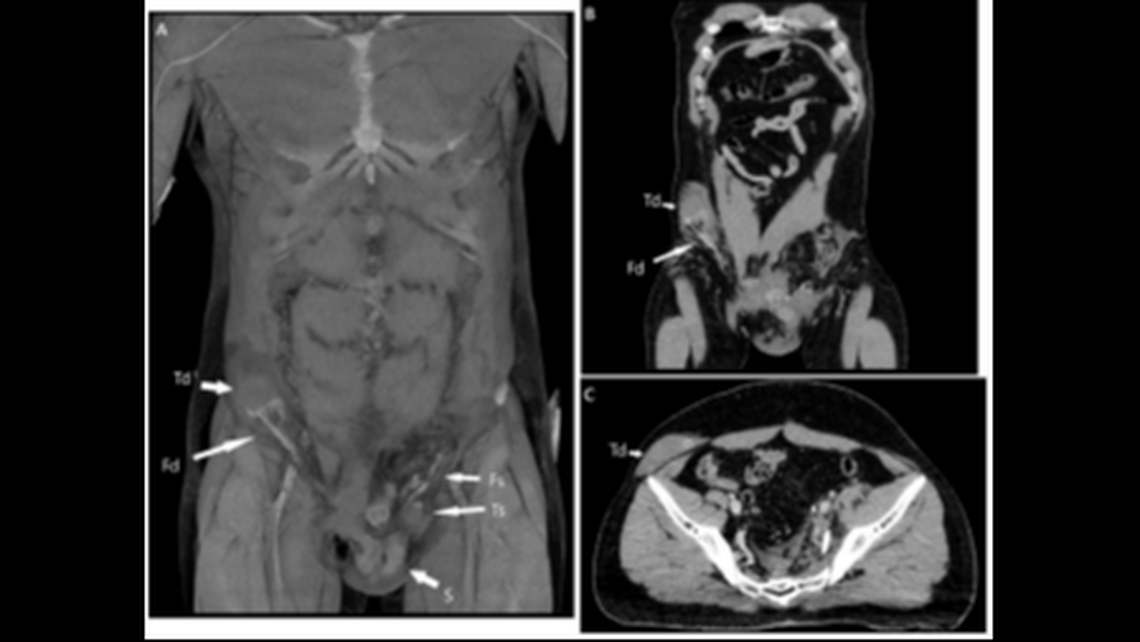

The doctors decided to take a closer look using a CT scan.

On the right side of the man’s body, lodged in the upper portion of the pelvis past the bladder, was his other testicle, fully intact, according to the report.

The doctors used a Doppler signal, a type of ultrasound that shows blood movement through blood vessels, to confirm the testicle was unharmed, despite its rogue journey north.